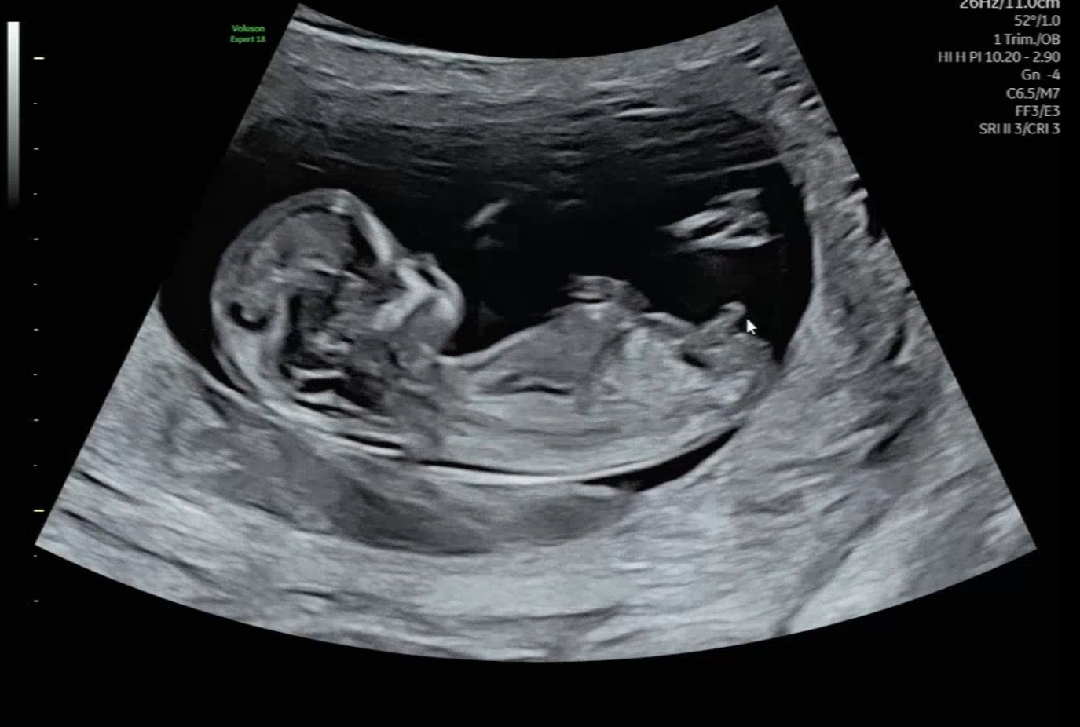

12주차 각도법 봐주세요~

딸일까요 아들일까요? ㅎㅎㅎ

아들같아여

아들이에요

끝에 갈고리모양 아들이에요

아들같아용